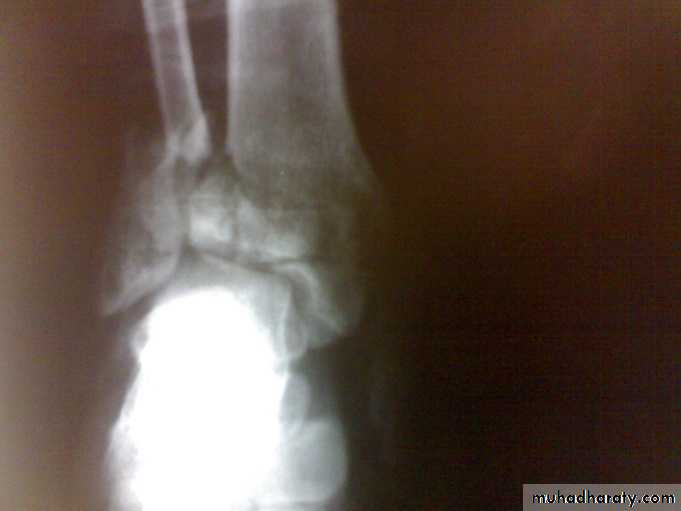

Zakho hospital Orthopedics Dr. MuthanaComminuted fractures of the tibial plafond (Pilon fracture)

Severe axial compression of the ankle (FFH).Shattering of ankle joint surface.

Secondary Osteoarthritis is common.